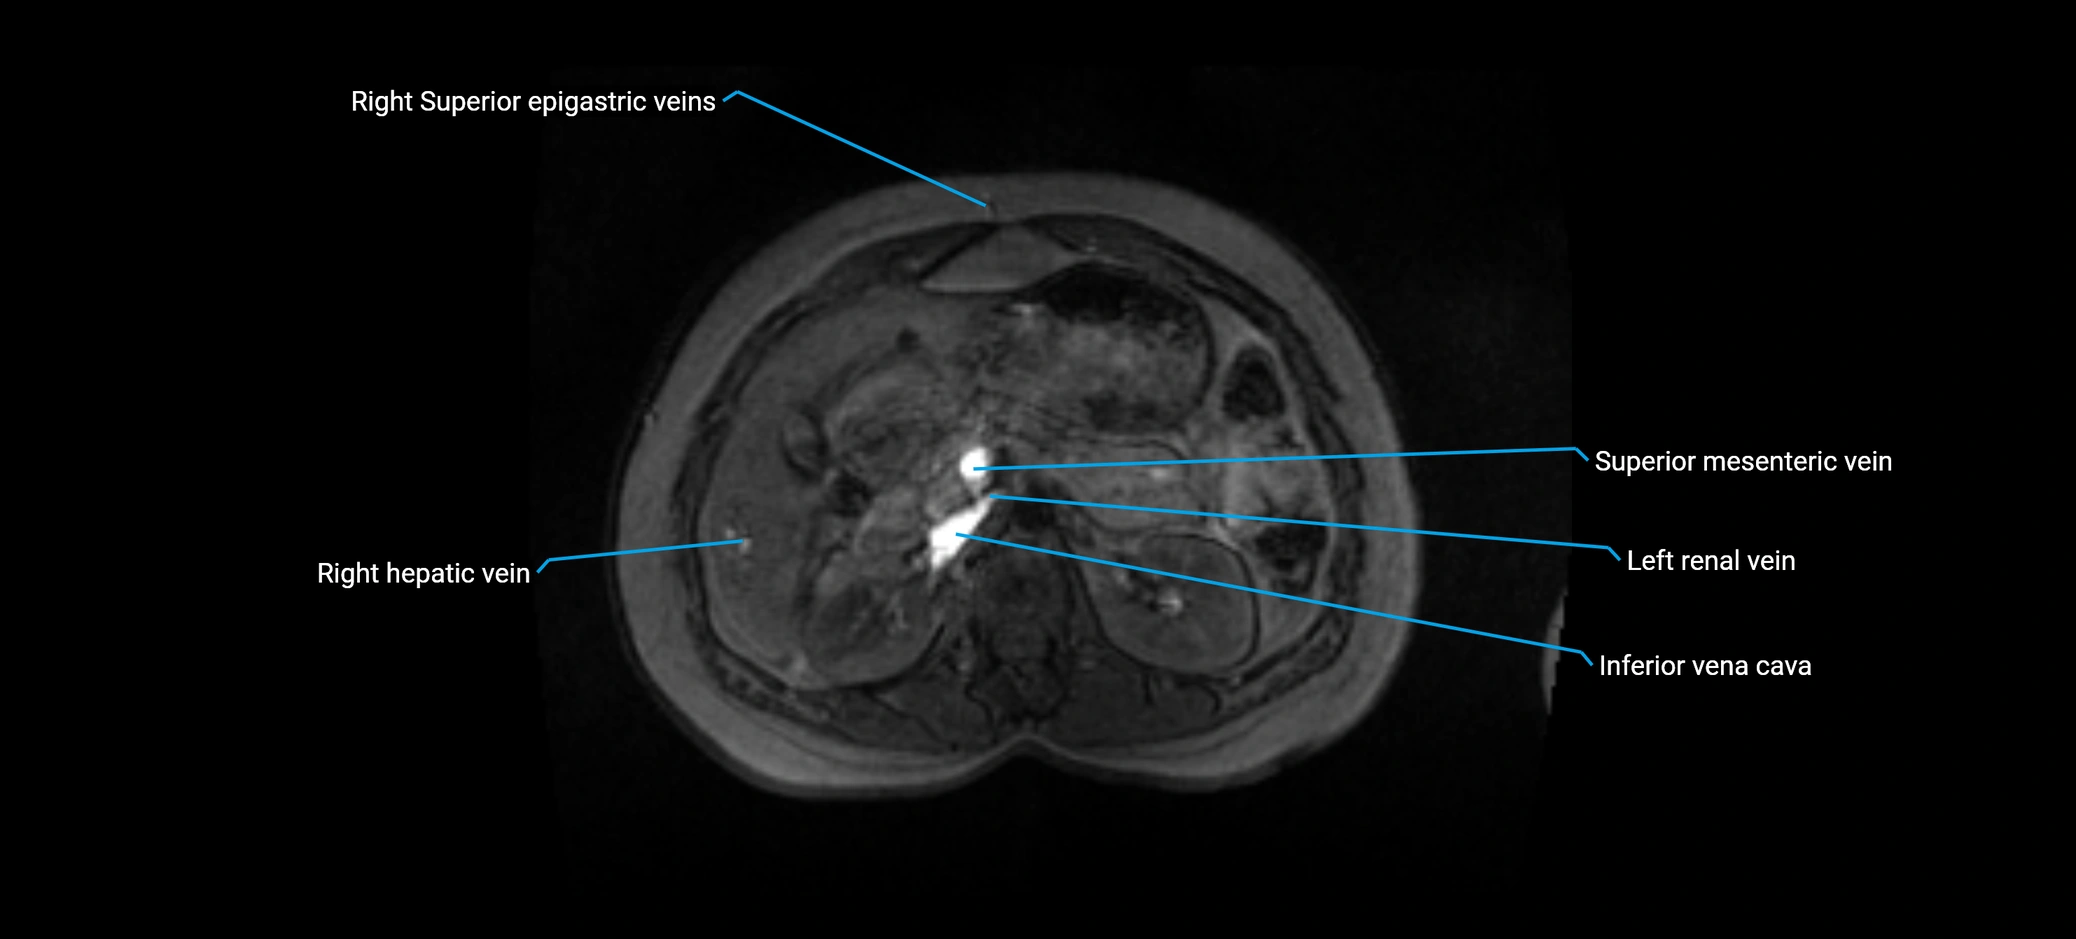

MRI image

image